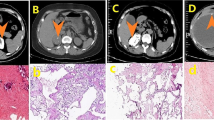

Adrenal cortical tumors showed cytoplasmic immunoreactivity in 96% of the cases for anti-calretinin, 89% for anti-melan-A and 92% for anti-inhibin, 20% for anti-BCL-2, and 5% for anti-c-kit. Immunoreactivity with anti-calretinin, anti-melan-A, and anti-inhibin was identified in 92%, 75%, and 92% of adrenocortical carcinomas and 100%, 100%, and 93% of adenomas, respectively (Table 2). Among the three adrenal cortical markers tested, calretinin immunoreactivity tended to be the most sensitive and more intense and diffuse in staining pattern than melan-A and inhibin (Fig. 1). In addition to cytoplasmic staining, nuclear immunostaining was also seen frequently with calretinin and less frequently with melan-A immunostaining (Fig. 1). Although carcinomas were slightly less immunoreactive than adenomas, no single adrenal cortical tumor was negative for all three markers or positive for only one marker. BCL-2 cytoplasmic immunoreactivity was detected only in three cases (30%) of adrenocortical carcinomas and 2 of 15 (13%) adrenocortical adenomas. C-kit immunoreactivity was detected in 1 of 9 (11%) adrenocortical carcinomas and 0 of 13 adrenocortical adenomas.

Pheochromocytomas were generally negative for calretinin, with the exception of the ganglioneuroma areas in composite pheochromocytomas (Fig. 2), and were negative for inhibin. Focal to 1+ melan-A reactivity was present in two pheochromocytomas (11%). BCL-2 cytoplasmic immunoreactivity was detected in 12/14 (86%) pheochromocytomas (Fig. 3). Focal c-kit immunoreactivity was detected in 2 (14%) of 14 pheochromocytomas. In extraadrenal paragangliomas, 5 of 20 cases (25%) were positive for calretinin (F+ to 2+), 1 of 19 (5%) for melan-A (1+), 3 of 19 (16%) for inhibin (F+ to 1+), 5 of 13 (38%) for BCL-2 (1+ and 2+), and 1 of 12 (8%) for c-kit (1+) (Table 1). All layers of the normal adrenal cortex, when present adjacent to the adrenal tumors, were variably positive for calretinin, melan-A, and inhibin without specific zonal staining pattern (Fig. 4). BCL-2 immunoreactivity was present primarily in normal adrenal medulla and lymphocytes adjacent to or entrapped in the adrenal tumors (Fig. 3). In contrast to the strong reactivity in the medulla, weak and rare granular cytoplasmic BCL-2 immunoreactivity was occasionally seen in the cortex. No c-kit immunoreactivity was detected in any normal adrenal cortex and medulla.